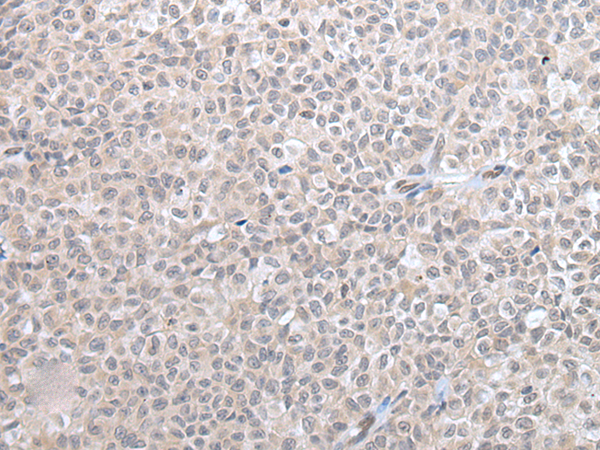

分类: 科研抗体货号: P12733别名: GAS应用: IHC反应种属: Human, Mouse, Rat

分类: 科研抗体货号: P12742别名: HOX3; cp19; HOX3E应用: WB,IHC反应种属: Human, Mouse

分类: 科研抗体货号: P12752别名: PYHIN2; IFNGIP1应用: IHC反应种属: Human